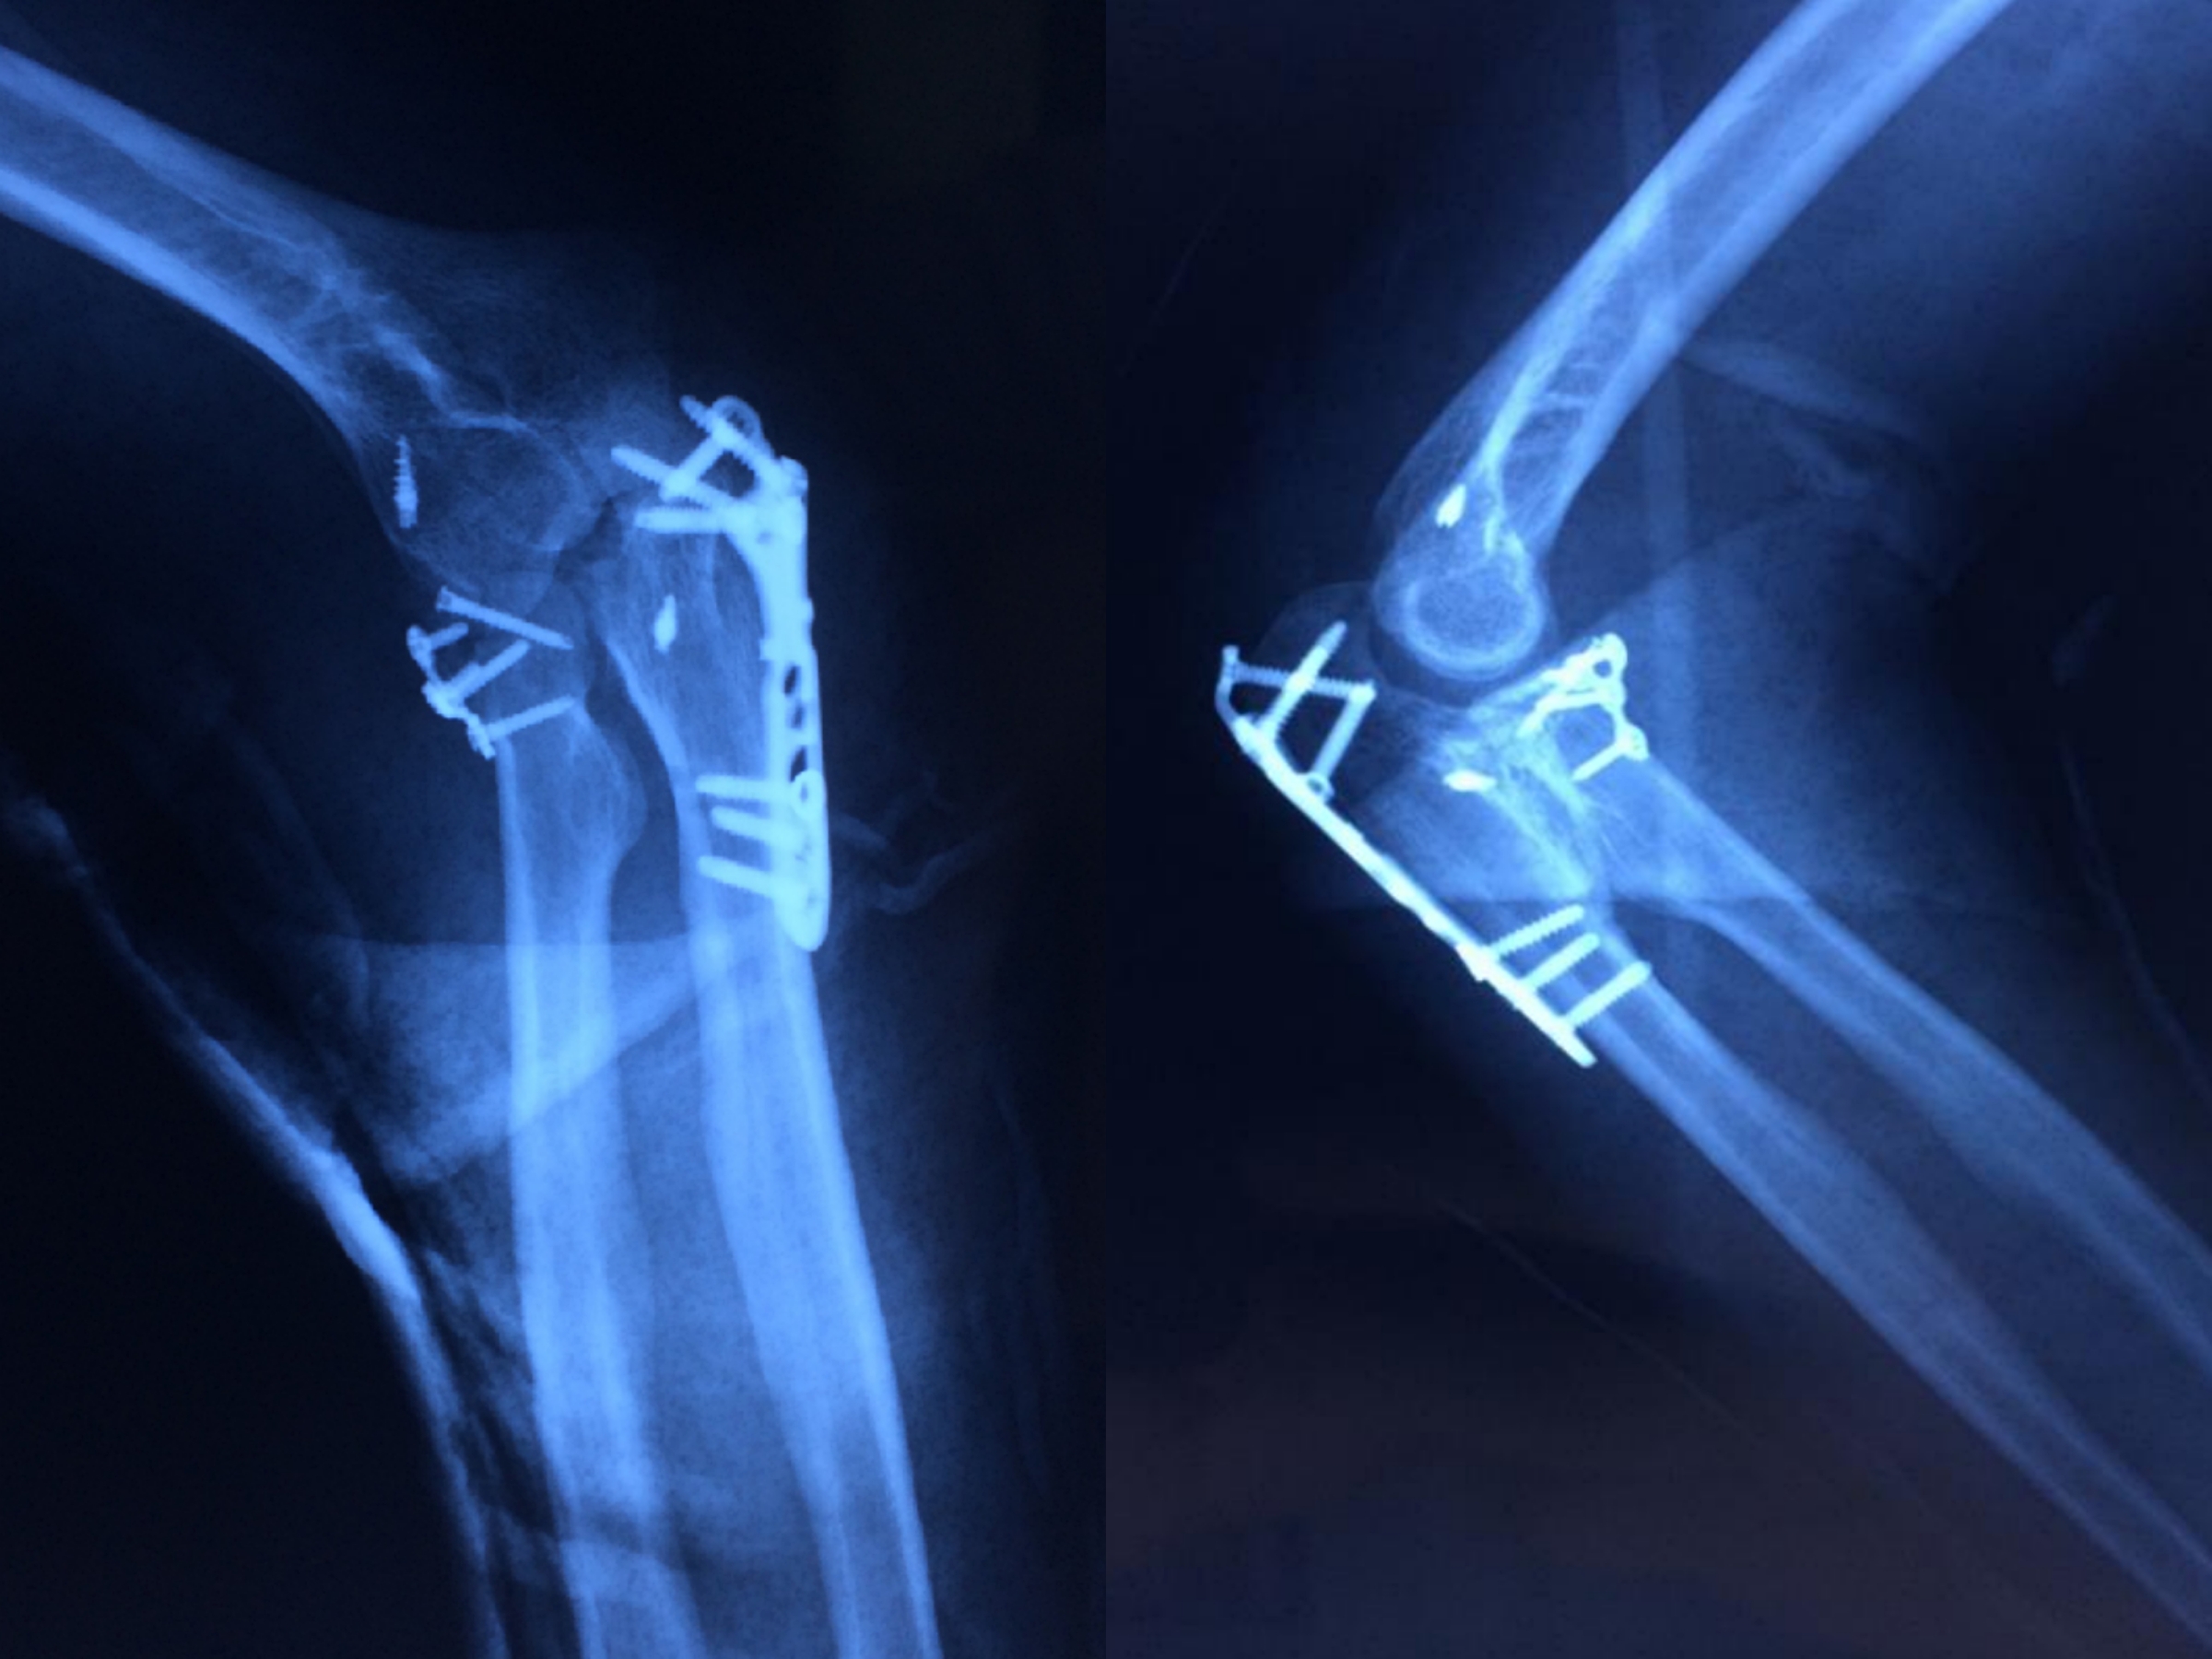

患者男性,42岁,于2019年12月6日摔伤,造成尺骨鹰嘴骨折伴肘关节脱位,4日后入院治疗。

1591340268903749.jpg

▲患者入院时影像资料

郑金龙主任表示将此病例诊断为经鹰嘴骨折肘关节后脱位,是由于患者具有以下几个特点:鹰嘴骨折且伴有冠突骨折,桡骨小头部分骨折,整个肘关节是后脱位,肱桡关节和肱尺关节都是破坏不稳定的。在治疗上选择了肘关节后入路,一个切口可以处理三个骨折部位,手术顺序先采用张力带固定处理冠状突骨折,再用解剖板固定桡骨小头骨折,用锚钉修复外侧副韧带,最后处理尺骨鹰嘴的粉碎性骨折。